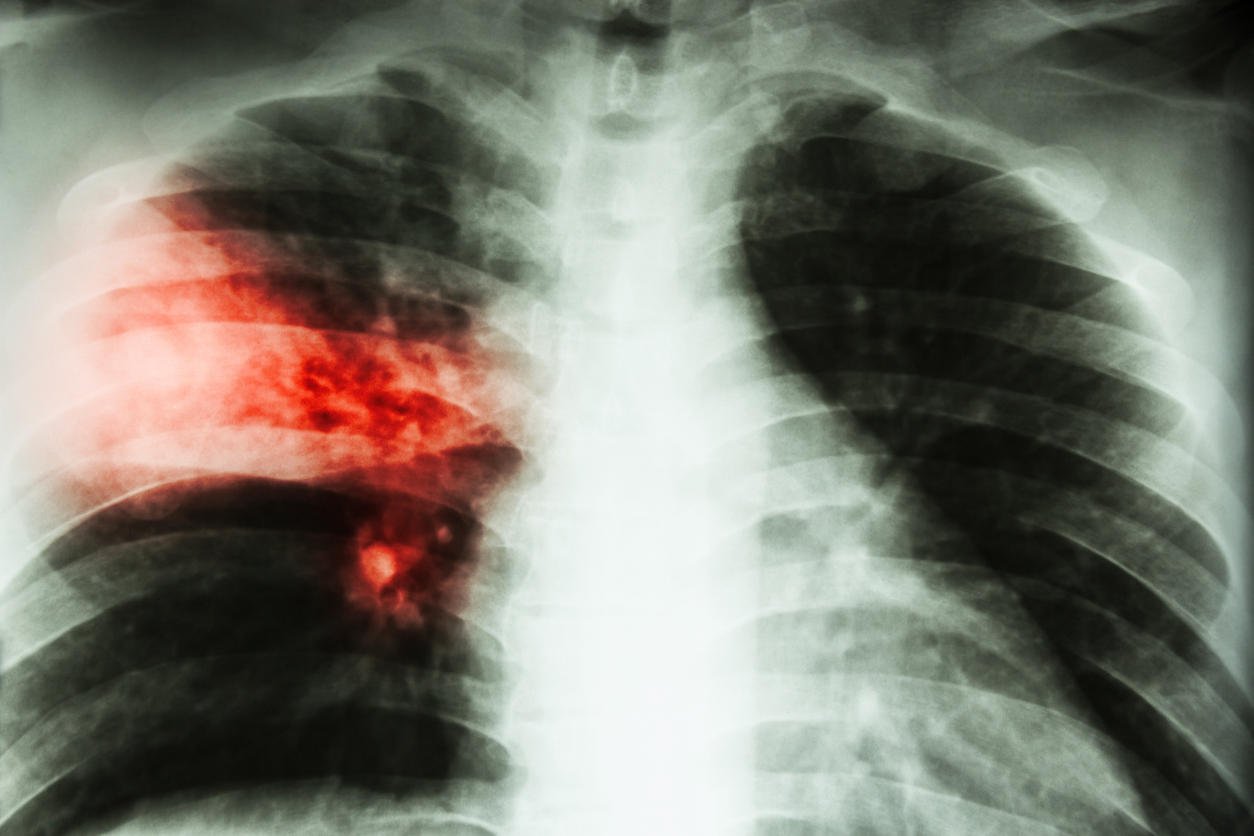

lobar pneumonia film chest x-ray show alveolar infiltration at right middle lobe due to tuberculosis infection

Istock